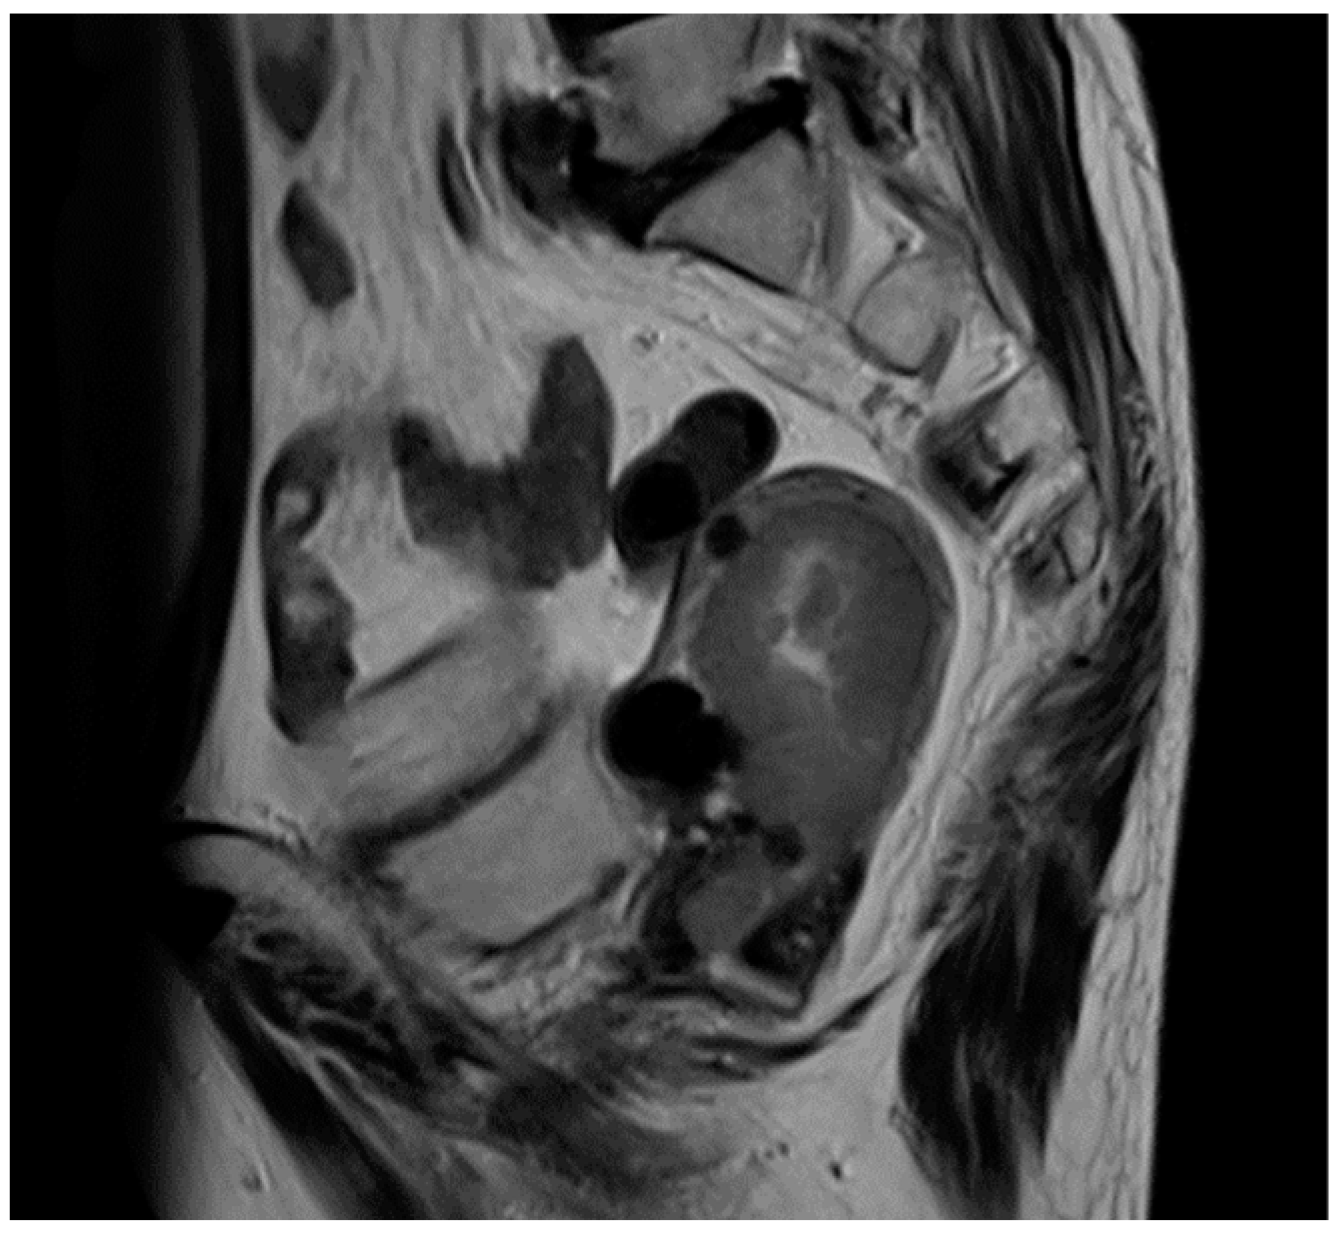

2. Case Presentation